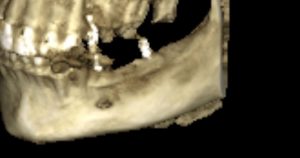

Теперь возьмём клинический случай (нижняя челюсть, отсутствия 35, 36, 37 зубов, атрофия альвеолярного гребня по ширине):

и рассмотрим его через парадигму методологического редукционизма. Или, если хотите, сквозь Бритву Оккама.

Мы имеем относительно небольшой дефект, не позволяющий, однако, установить имплантаты правильного размера в правильное положение. И два варианта остеопластической операции, НКР и АТККФ.